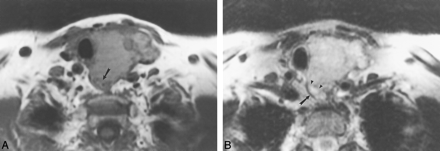

This 66-year-old man had direct EI by laryngeal carcinoma, resulting in a tracheo-esophageal fistula.

A, Axial T1-weighted image (600/17) shows a mass that surrounds the esophagus (arrows) by approximately 270o. The fat plane between the mass and the esophagus is obliterated. The esophageal lumen contains air.

B, Axial T2-weighted image (4000/80) shows focal increased signal (arrow) in the esophageal wall adjacent to the mass.